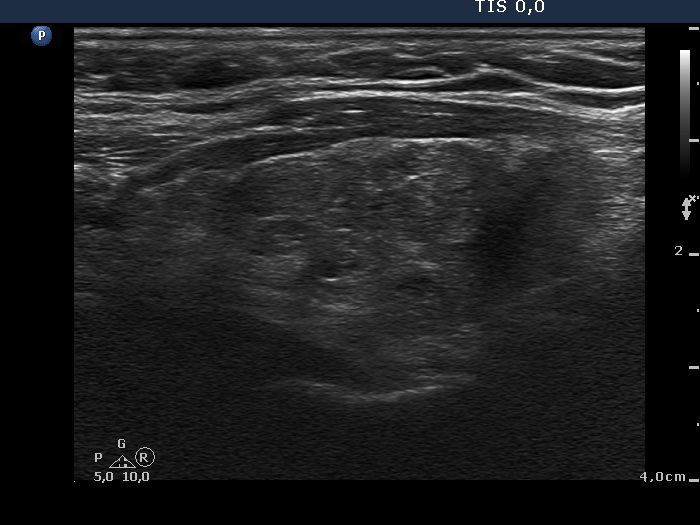

Discrete lesion or nodule in Hashimoto's thyroiditis - case 14 (377) (ultrasonographic picture 7)

Right lobe, longitudinal scan